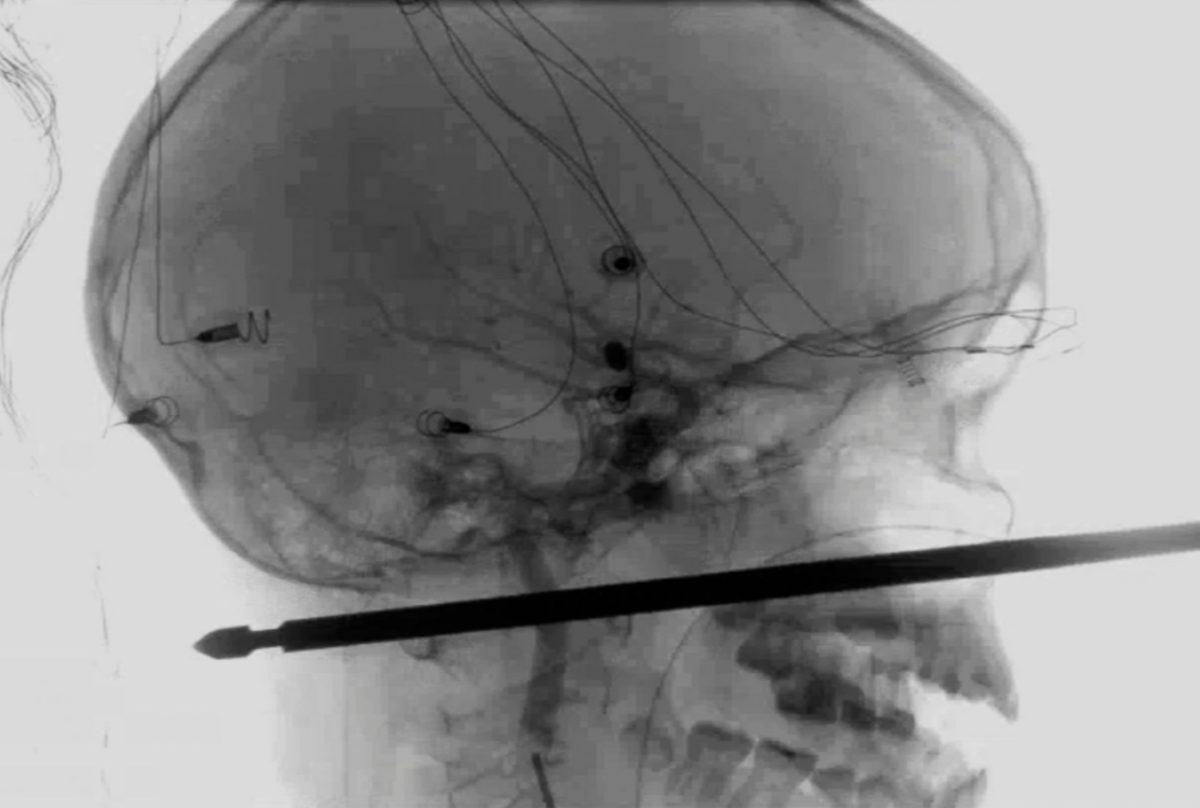

- Bir adamın arkasından atılan ateş maşası, arkadan girip önden çıkmış.

- Ağaç evden et şişinin üzerine düşen bir çocuk.

Hayatta kalmayı başarmış.